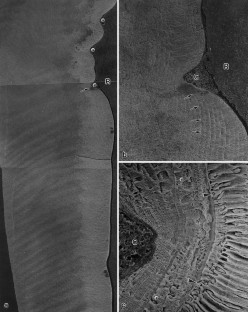

We studied the structural changes in the enamel of mandibular third molars of miniature pigs administered a daily oral dose of 2 mg NaF (approximately 0.9 mg of fluoride) per kg body weight (added to the feed) for 1 year. The treatment period covered most of the secretory stage and the entire post-secretory stage of amelogenesis of the M3. The enamel of the molars from the fluoride-fed pigs appeared opaque and chalky, and the erupted portions were stained brown. The underlying histopathological change was a pronounced subsurface hypomineralization of the enamel beneath a thin surface rim of higher mineral content. This enamel hypomineralization was attributed to a fluoride-induced impairment of the process of enamel maturation. The most conspicuous finding in the fluorotic enamel was the presence of numerous pit-type hypoplastic defects, denoting a marked fluoride-induced disturbance also of the secretory stage of amelogenesis. Microradiography and scanning electron microscopy revealed an enhanced incremental pattern in the outer enamel of the fluorotic molars. Typically, the bottom of larger hypoplastic defects was underlain by a broad, grossly accentuated incremental line. Occurrence of larger hypoplasias was further associated with the presence of aprismatic enamel, the formation of which was attributed to a loss of the prism-forming (distal) portion of the Tomes’ processes of secretory ameloblasts. The findings in the miniature pigs closely parallel earlier observations on fluorotic enamel of free-ranging deer and wild boar from fluoride-polluted areas.

Fig. 6a–c

Fig. 7a–c